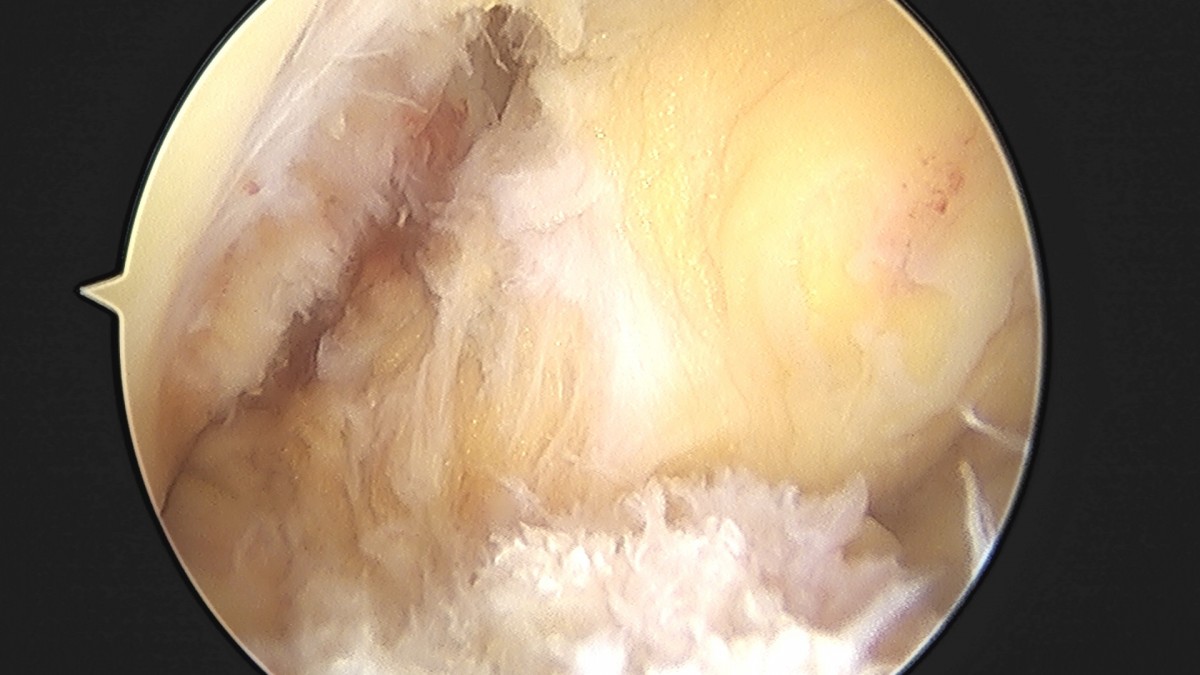

이재상원장님 무릎 전방십자인대 재건술 김태O 환자

작성자 최고관리자 댓글 0건 조회 679회 작성일 25-09-16 16:23